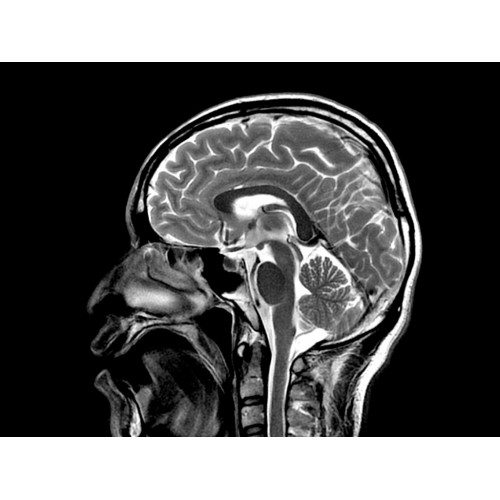

МР-томограф с широким туннелем Optima MR450w является настоящей рабочей лошадкой и может эффективно обслуживать большее число пациентов. Томограф обеспечивает одновременно удобство пациента, продуктивность работы, отличное качество изображения. В этой МРТ-системе инженерам компании удалось без компромиссов совместить необходимый объем перемещения с удивительно высоким качеством изображения.

Благодаря принципиально новым технологиям мы расширили возможности МР-томографов с широкими туннелями, совместив непревзойденное качество изображений с высокой производительностью при широком — 50 см — поле зрения.

МР-томограф Optima MR450w позволяет получать изображения исключительно высокого качества, которые помогают установить диагноз. Чтобы удовлетворить ожидания клиентов в отношении высокого качества, в МР-томографе Optima MR450w были сохранены дополнительные возможности платформы Discoverу, привнесшие в его работу универсальность и мощь.

• Цифровой РЧ-приемник OpTix — эксклюзивная оптическая РЧ-система увеличивает четкость сигнала и его интенсивность, формируя чистые и резкие изображения.